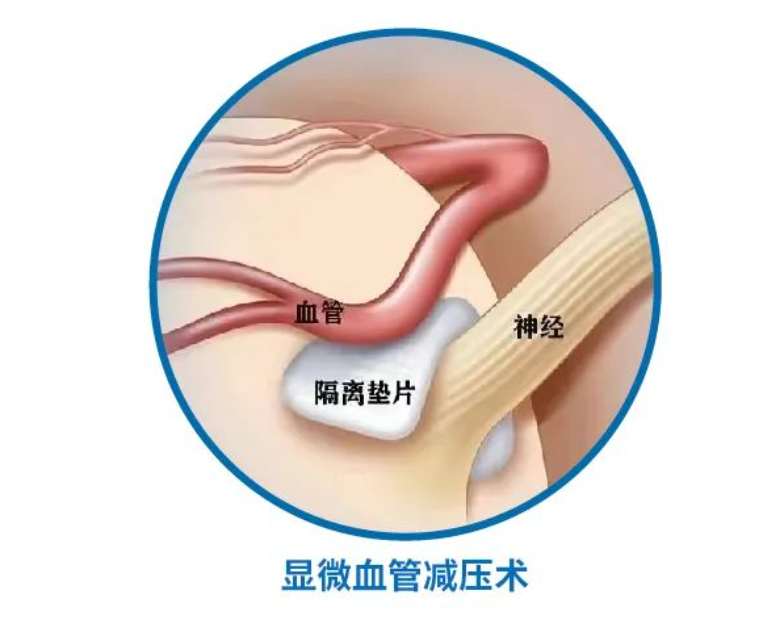

微血管减压术在面肌痉挛患者中的应用

微血管减压术在面肌痉挛患者中的应用

总结背景:面肌痉挛是一种运动性神经紊乱,表现为面部神经所支配的肌肉发生短暂的或持续的无意识收缩。发病率约为11/十万人。